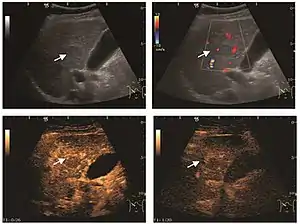

These lesions have various patterns (hypo or hyperechoic) with at least 1 cm diameter. They are hepatocytes with dysplastic changes, but without clear histological criteria for malignancy. They are divided into low-grade dysplastic nodules, where cellular atypia are mild and high-grade dysplastic nodules with moderate or severe cellular atypia, but without any established signs of malignancy. Occasionally, well-differentiated HCC foci can be identified in high-grade dysplastic nodules (appearance called "nodule in nodule") . Most authors accept the carcinogenesis process as a progressive transformation of DN from low-grade to high-grade and into HCC. The nodule's vasculature changes progressively, correlated with the degree of malignancy, and it is characterized by decrease until absence of portal venous input and by increase of arterial intratumoral input. Neoformation vessels occur with increasing degree of dysplasia. Arterial neovascularization is enhanced in a chaotic and explosive way, while normal, arterial and portal vasculature continues to decline. High-grade dysplastic nodules are hypovascularized both arterial and portal phases, while early HCC nodules may have similar arterial pattern with the surrounding parenchyma or exacerbated, and portal hypovascularization. In moderate or poorly differentiated HCC (classic HCC) tumor nutrition is performed only by neoformation vessels (abundant), the normal arterial and portal vasculature completely disappearing. This behavior of intratumoral vascularization is typical for HCC and is the key to imaging diagnosis.

B-mode ultrasonography is unable to distinguish between regenerative nodules and borderline lesions such as dysplastic nodules and even early HCC. Doppler examination also has a low sensitivity in differentiating dysplastic nodules from early HCC. Doppler signal may be absent in both regenerative and dysplastic nodules. Some authors indicate the presence of venous type Doppler flow which reflects the portal venous nutrition of the nodule as a characteristic feature of dysplastic nodules and early HCC (Minami & Kudo, 2010). Other authors noticed the presence of an arterial flow with small frequency variations and a normal resistivity index. On CEUS examination both RN and DN may have quite a variable enhancement pattern. Generally, both nodules enhances identically with the surrounding liver parenchyma after UCAs injection. Dysplastic nodules are hypovascular in the arterial phase. In case of highgrade dysplastic nodule sometimes a hypervascularization can be detected, but without associating "wash out" during portal and late CEUS phases. In these cases, biopsy may clarify the diagnosis.

The suggestive appearance of early HCC on 2D ultrasound examination is that of hypoechoic nodule, with distinct pattern, developed on cirrhotic liver. Hypoechoic appearance is characteristic of moderate/poorly differentiated HCC, with low or absent fatty changes. Rarely, HCC may appear isoechoic, consist of a tumor type with a higher degree of differentiation and therefore with slower development. Another common aspect is "bright loop" or "nodule-in-nodule" appearance, hypoechoic nodules in a hyperechoic tumor.

Spectral Doppler characteristics of early HCC overlap those of the dysplastic nodule, as they are represented by the presence of portal venous signal type or arterial type with normal RI (well differentiated HCC) or increased RI (moderately or poorly differentiated HCC). The CFM exploration identifies a chaotic vessels pattern.

On CEUS examination, early HCC has an iso- or hypervascular appearance during the arterial phase followed by wash out during portal venous and late phase. There are studies showing that the wash out process is directly correlated with the size and features of neoplastic circulatory bed. Thus, highly differentiated HCC illustrates the phenomenon of late or even very late "wash out" while poorly differentiated HCC has an accelerated wash out at the end of arterial phase. It is therefore mandatory to analyze all these three phases of CEUS examination for a proper characterization of liver nodules. Tumor wash out at the end of the arterial phase allows the HCC diagnosis with a predictability of 89.5%. Some authors consider that early pronounced contrast enhancement of a nodule within 1–2 cm developed on a cirrhotic liver is sufficient for HCC diagnosis. These results prove that for a correct characterization of the lesions it is necessary to extend the examination time to 5 minutes or even longer.